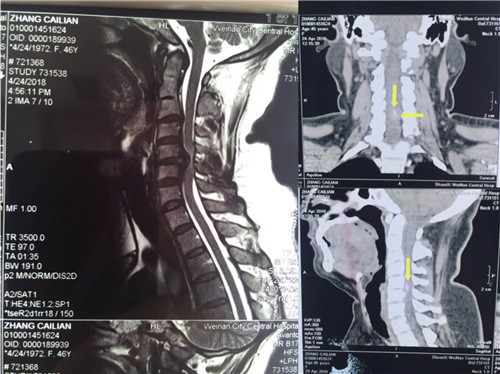

入院后,骨一科医师对患者做进一步检查。颈椎CT显示,颈5/6椎间盘突出,颈3/4、4/5、6/7椎间盘突出;颈椎MR显示,颈4/5、6/7椎间盘突出,颈5/6椎间盘突出并椎管狭窄。

术前

术后